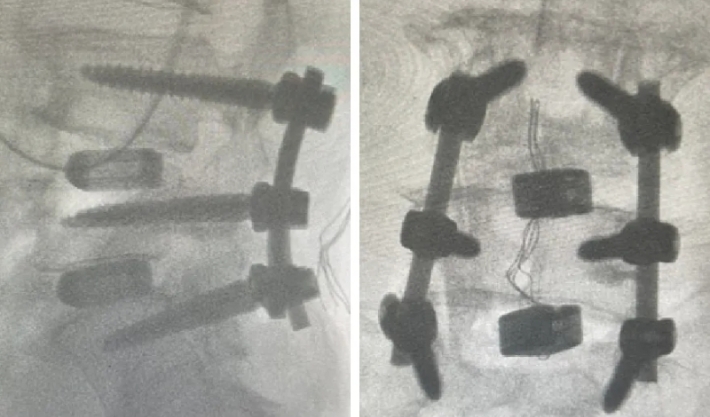

近日,Beat365中国唯一官方网站第六附属医院(新疆维吾尔自治区骨科医院)脊柱外三科在医疗技术上取得新的突破,成功为两位腰椎手术患者利用3D打印融合器实施了腰椎椎体间融合术,患者术后恢复良好。

随着人口老龄化趋势不断加剧,腰椎间盘突出症、腰椎管狭窄症、腰椎滑脱等已成为常见的退行性脊柱疾病之一,严重影响中老年人的生活质量和身心健康。腰椎椎体间融合术是解决退行性脊柱疾病的常用手术方式之一。然而,在老年人骨质疏松、骨含量低的情况下,容易发生植骨融合失败的后遗症。3D打印融合器能有效解决这一问题。这两例手术中所使用的融合器,是通过3D打印技术制造的一种新型的多孔钛合金椎间融合器,它的微观和宏观结构模仿了人体椎体的天然骨小梁,更加贴合人体结构。同时,进一步优化了材料表面,使其具有更好的生物相容性和成骨活性,能够帮助新生骨快速长入融合器,加速愈合。该融合器还很适合微创手术,不需要再植入自体骨或其他骨修复材料,不仅提高了治疗效果,还减少了患者的手术创伤。

随着3D打印技术的不断成熟,这一技术有望在更多脊柱疾病治疗中推广应用。作为全疆最先运用3D打印脊柱椎间融合器的科室,该院脊柱外三科将继续紧跟时代步伐,积极应用数字化辅助技术和医工结合技术,致力于实现个体化、精准化的治疗,为患者带来更加安全、高效、舒适的医疗服务体验。